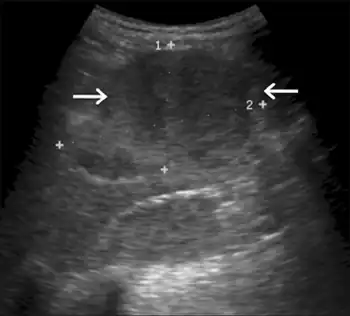

Hepatomegaly

Impairment in the liver's ability to perform gluconeogenesis leads to clinically apparent hepatomegaly. Without this process, the body is unable to liberate glycogen from the liver and convert it into blood glucose, leading to an accumulation of stored glycogen in the liver. Hepatomegaly from the accumulation of stored glycogen in the liver is considered a form of non-alcoholic fatty liver disease. GSD I patients present with a degree of hepatomegaly throughout life, but severity often relates to the consumption of excess dietary carbohydrate. Reductions in the mass of the liver are possible, since most patients retain residual hepatic function that allows for the liberation of stored glycogen at a limited rate.

GSD I patients often present with hepatomegaly from the time of birth. In fetal development, maternal glucose transferred to the fetus prevents hypoglycemia, but the storage of glucose as glycogen in the liver leads to hepatomegaly. There is no evidence that this hepatomegaly presents any risk to proper fetal development.

Hepatomegaly in GSD type I generally occurs without sympathetic enlargement of the spleen. GSD Ib patients may present with splenomegaly, but this is connected to the use of filgrastim to treat neutropenia in this subtype, not comorbid hepatomegaly. Hepatomegaly will persist to some degree throughout life, often causing the abdomen to protrude, and in severe cases may be palpable at or below the navel. In GSD-related non-alcoholic fatty liver disease, hepatic function is usually spared, with liver enzymes and bilirubin remaining within the normal range. However, liver function may be affected by other hepatic complications in adulthood, including the development of hepatic adenomas.

Once the diagnosis is suspected, the multiplicity of clinical and laboratory features usually makes a strong circumstantial case. If hepatomegaly, fasting hypoglycemia, and poor growth are accompanied by lactic acidosis, hyperuricemia, hypertriglyceridemia, and enlarged kidneys by ultrasound, GSD I is the most likely diagnosis. The differential diagnosis list includes glycogenoses types III and VI, fructose 1,6-bisphosphatase deficiency, and a few other conditions (page 5), but none are likely to produce all of the features of GSD I.